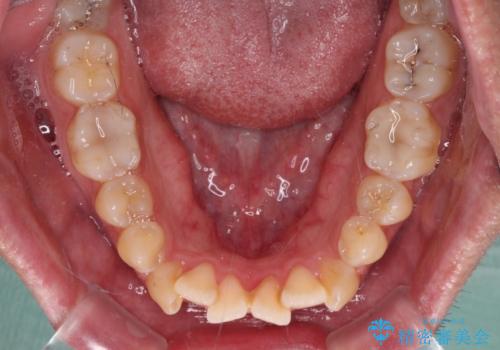

開咬とデコボコを整える インビザライン矯正治療

- 前歯の開咬と叢生を気にして来院された患者様です。

開咬の治療は、前歯を閉じるように動かすとともに、上下臼歯を圧下(骨内にめり込ませる)させることで進めて行きます。

オープンバイトは舌の突出癖により誘発され、治療後も突出癖が残っている容易に後戻りしてしまいます。

治療期間を短縮するためにも、舌突出癖の改善が極めて重要となります。